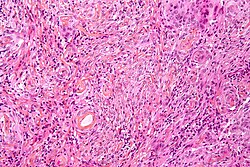

| Metastasis | sharp interface with brain, often glandular, +/-nucleoli, no glial processes | often cerebellular, well-circumscribed | usu. old | often suspected to have metastatic disease | TTF-1, CK7, CK20, BRST-2 | File:Metastatic adenocarcinoma - cerebellum - very low mag.jpg Metastasis. (WC) |